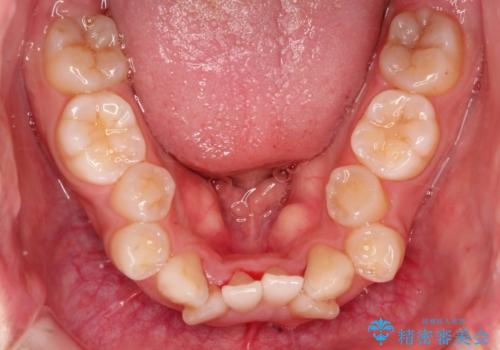

骨格的要因を背景にもつ不正咬合のため、歯列矯正単独での改善は困難と判断しましたが、患者さんとの相談の結果、歯列矯正単独で可能なところまで一緒に頑張りましょうということで、治療をすすめました。

シビアな叢生や開咬も改善することができ、想像以上の改善に時間をかけた甲斐があったと満足していただけました。